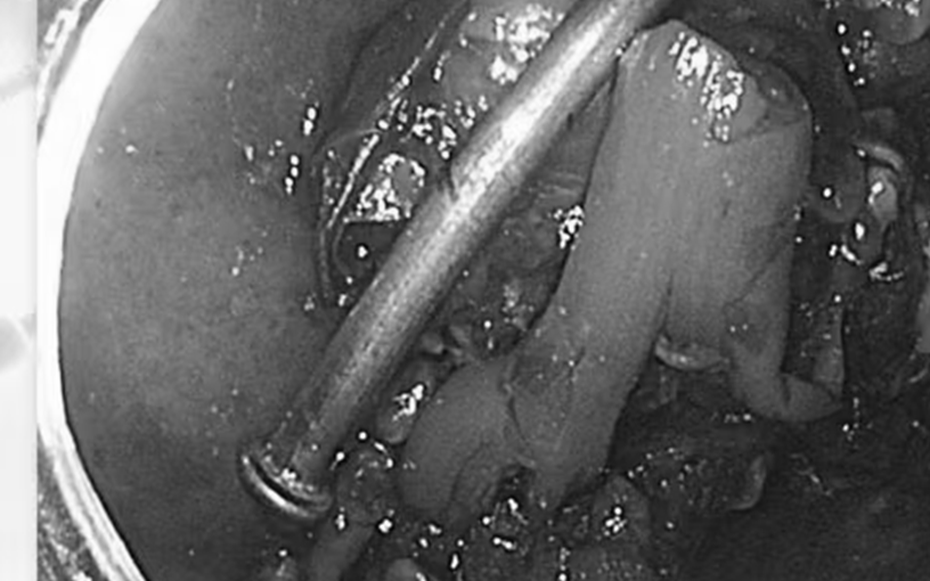

Hình ảnh đinh dài 5cm được lấy ra từ trong bụng bệnh nhi.

Ê-kíp đã gắp thành công chiếc đinh ra ngoài, không gây tổn thương đường tiêu hóa. Bé tỉnh táo ngay sau thủ thuật.